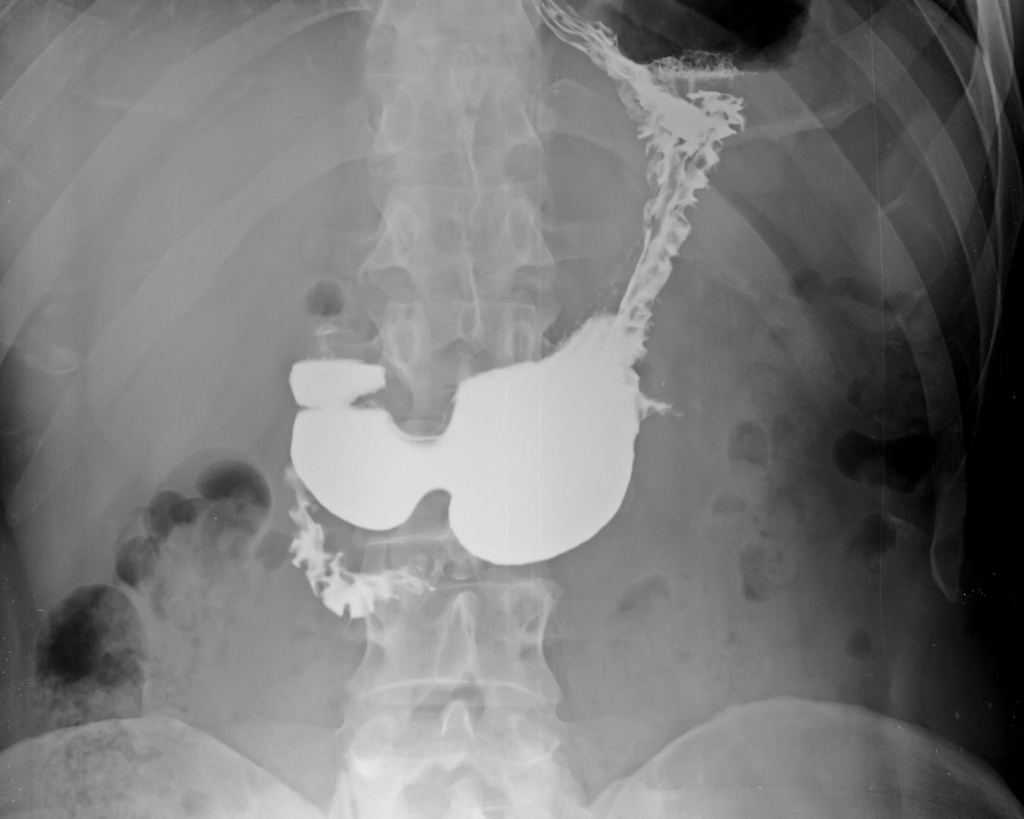

Рентген верхнього відділу ШКТ дозволяє оцінити не лише анатомію, а й функціонування цих органів у реальному часі. Це контрастне рентгенологічне дослідження, яке допомагає лікарю побачити, як проходить контрастна речовина, чи немає звужень, деформацій або порушень моторики.

Під час обстеження пацієнт приймає контрастну речовину, яка робить стравохід, шлунок і дванадцятипалу кишку видимими на рентгенівських знімках. Лікар спостерігає за проходженням контрасту та виконує знімки у різних положеннях тіла.

Це дозволяє:

оцінити форму та положення органів;

виявити звуження або розширення;

побачити порушення ковтання;

визначити рефлюкс;

виявити деформації стінок;

оцінити моторику верхнього відділу ШКТ.

Дослідження проводиться поетапно, що дає повну картину функціонування травного тракту.